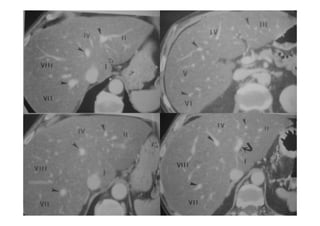

Ao nível dacabeça pancreática e do processo uncinado(u),a junção do ducto pancreático comum com o ducto biliar comum(seta curva) é definida.A artéria mesentérica superior situa-se anterior a aorta e posterior a junção do colo e corpo do pâncreas. Ao nível do colo pancreático,é visível o ducto pancreático principal(seta aberta). A v. porta situa-se imediatamente posterior ao colo do pâncreas e lateral à artéria mesentérica superior. (Ponta de seta)Artéria pancreato duodenal antero superior.

Ao nível docorpo pancreático observa-se um curto segmento do ducto pancreático(ponta de seta). Veia renal esquerda(seta curva). Corpo e cauda pancreática(seta aberta maior). Vv hepáticas não contrastadas.

Ducto pancreático V porta ams Ductocolédoco Ducto colédoco Ducto pancreático aorta Veia renal ampola vms Tronco gastrocólico